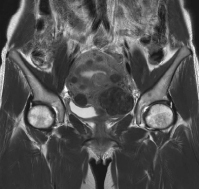

MRI検査

男性器領域

- 前立腺

- 前立腺がん・前立腺肥大など

- 膀胱

- 膀胱がんなど